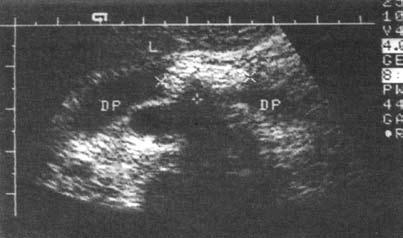

Ультразвуковое исследование (сканирование) является одним из наиболее информативных и притом неинвазивных методов исследования ПЖ и должно осуществляться во всех случаях, когда подозревается ее патология (рис. 137–139).

Датчик располагается в эпигастральной области и его перемещают соответственно проекции железы на области левого и правого подреберий. В норме ПЖ имеет ровные, четкие контуры и гомогенную структуру, а диаметр главного панкреатического протока не превышает 1,5–2 мм. При патологии может выявляться общее увеличение размеров органа с равномерным уменьшением эхоплотности, свидетельствующее об отеке. Уменьшение размеров железы, неоднородность структуры, наличие мелких участков уплотнения ткани, а также нечеткость контуров могут говорить о фиброзных изменениях в железе, а небольшие резко выраженные эхоположительные узелки – об очаговом обызвествлении паренхимы. Эхоструктуры высокой плотности, расположенные в протоке и дающие феномен «ультразвуковой дорожки», являются признаком внутрипротоковых конкрементов. Жидкостные образования (ложные кисты, вялотекущие абсцессы) представляются на эхограмме округлыми участками значительно пониженной эхоплотности с более или менее четкими контурами и дорсальным усилением. Хорошо сформированные ложные кисты с жидким содержимым имеют округлую или овальную форму, гомогенны и окружены четко выраженной капсулой. Содержимое несформировавшихся кист и абсцессов может быть неоднородным из‑за наличия в них, помимо жидкости, тканевых секвестров и детрита.

Рис. 139. Хронический панкреатит. Конкремент в просвете протока ПЖ (DP)